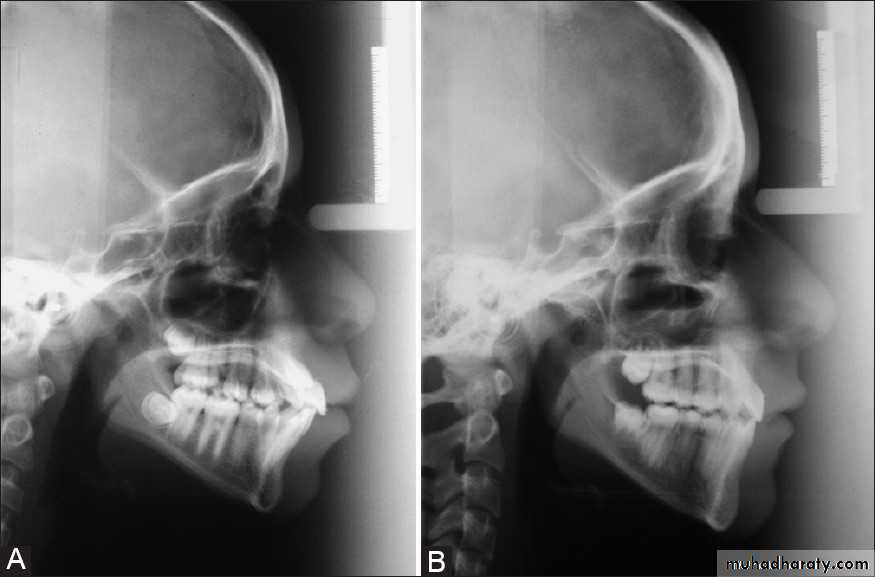

From the dental perspective, the severity of the dentoalveolar protrusion is best characterised by the interincisal angle.

• 125 degree- 115 degree = mild

• 115 degree- 105 degree = moderate

• <105 degree = severe.

Classification

Orthognathic surgery is required to correct significant skeletal problems using subapical osteotomies with extraction and with or without Genioplasty.Stability & Relapse